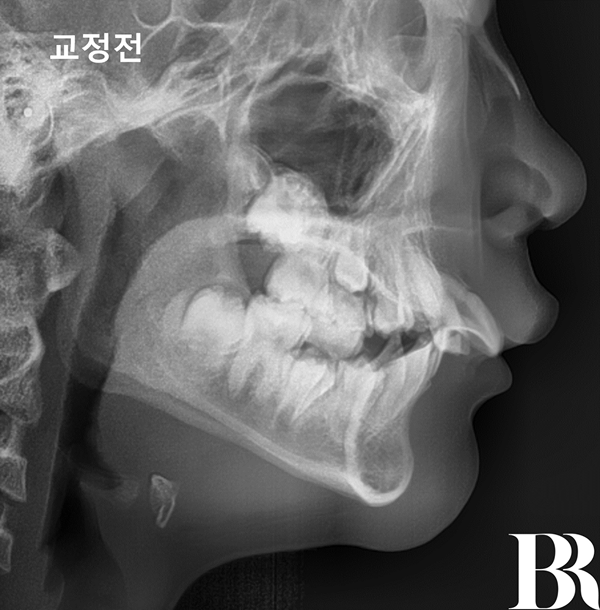

나이 : 12세

성별 : 남자

내원 이유 : 윗니가 뻗어 있다

치료방법 : 턱교정(1차교정) 엑티베이터 with 헤드기어

치료시작 : 2024년 7월

치료종료 : 2025년 11월

치료기간 : 1년 4개월

1년 4개월 간 이루어진

턱교정치료가 끝났습니다.

아래턱이 이쁘게 나왔고

윗니와 아랫니의 앞뒤 차이가

정상 범위 내로 줄어들었습니다.

발치교정을 요하지 않는

상태로 만들었습니다^^